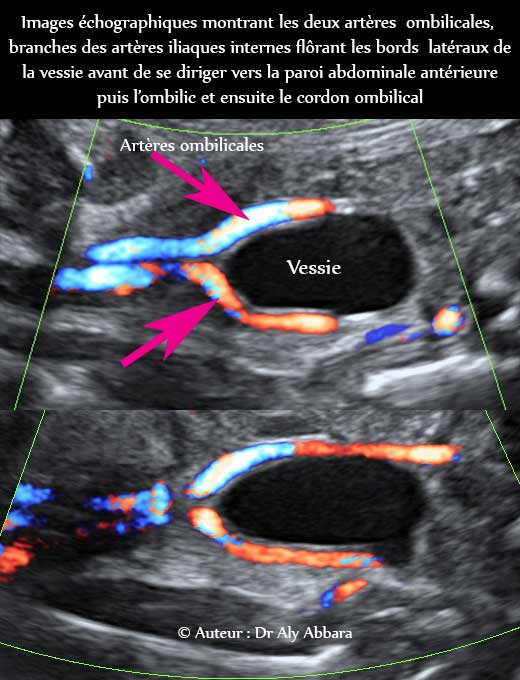

| Images échographiques montrant le trajet parcouru par les artères ombilicales dans le petit pelvis, dès leur origine des artères iliaques internes jusqu'à l'ombilic au niveau de la paroi abdominale antérieure. Au cour de ce trajet, les artères ombilicales effleurent les parois latérales de la vessie Fœtus âgé de 28 SA |